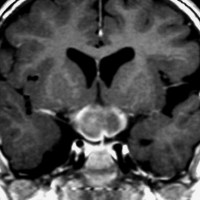

画像の特徴

幼児の視路の毛様粘液性星細胞腫です。T2強調画像(左側)で白く高信号に写るのが特徴です。ガドリニウム増強ではまだらになっていますが,均一に真っ白に高信号になることも多いです。乳幼児のものは,ドロドロに柔らかい腫瘍です。